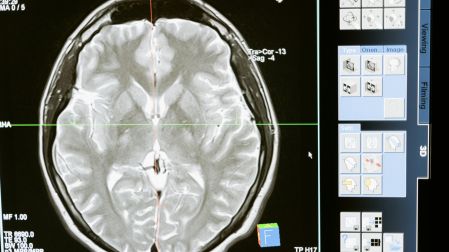

Por otro lado, Kalimba reveló tener epilepsia en el lóbulo frontal izquierdo es un trastorno del cerebro que ocurre cuando un grupo de neuronas envía una descarga de señales eléctricas, lo que provoca convulsiones que comienzan en la parte delantera del cerebro.

Los síntomas de la epilepsia en el lóbulo frontal izquierdo son: